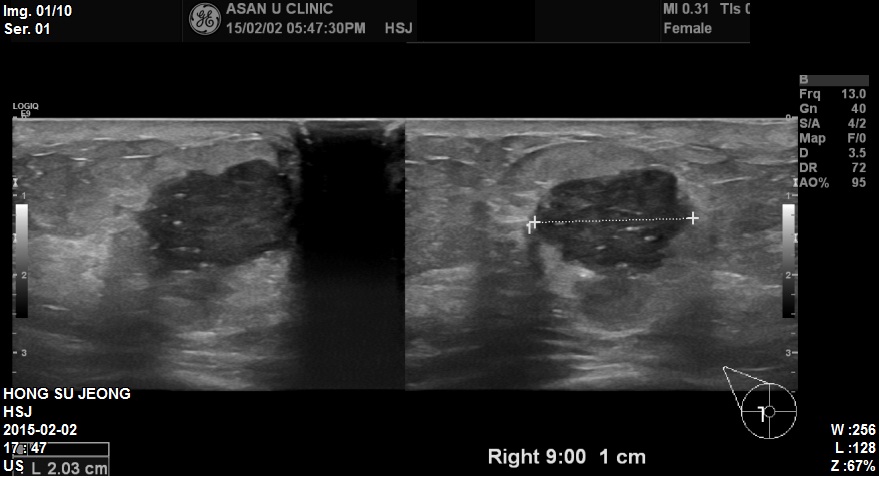

상기환자 우측유방에 만져지는 멍우리로 내원하신 59세 환자분이십니다.

본원에서 우측유방 9시방향에 2.03cm 혹 조직검사 시행하였고

겨드랑이에 임파절 비대소견보여 세침검사 진행하였습니다.

결과상 우측유방 침윤성유관암으로 진단되었고 겨드랑이까지 전이된상태였습니다.